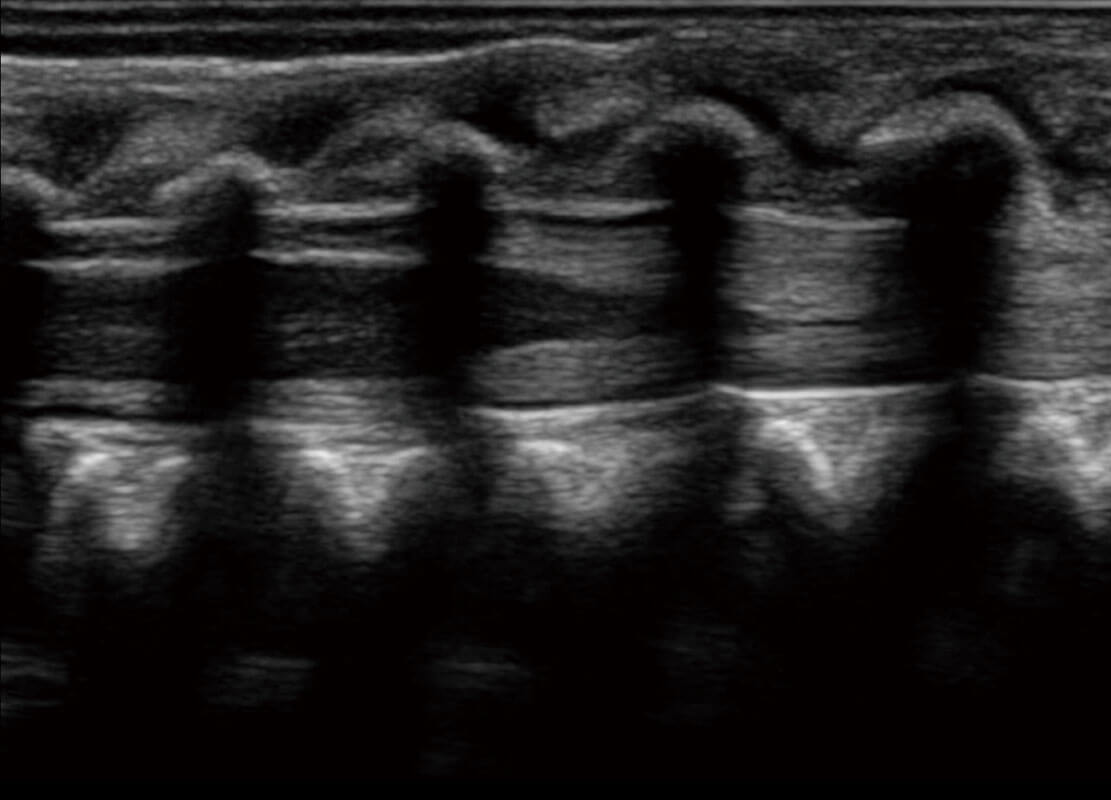

早孕-胎心

胎儿体循环